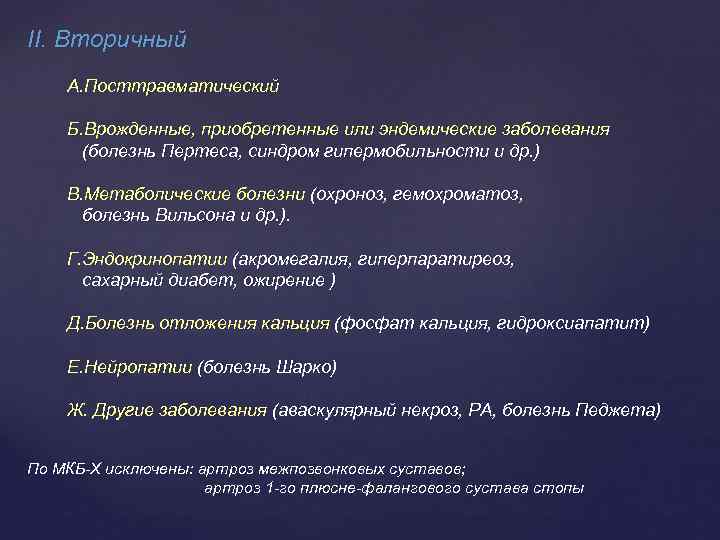

ПАССИВНАЯ ЗАЩИТА СУБХОНДРАЛЬНАЯ КОСТЬ ОА АКТИВНАЯ ЗАЩИТА МЫШЕЧНО-СВЯЗОЧНЫЙ АППАРАТ

ПАССИВНАЯ ЗАЩИТА СУБХОНДРАЛЬНАЯ КОСТЬ ОА АКТИВНАЯ ЗАЩИТА МЫШЕЧНО-СВЯЗОЧНЫЙ АППАРАТ